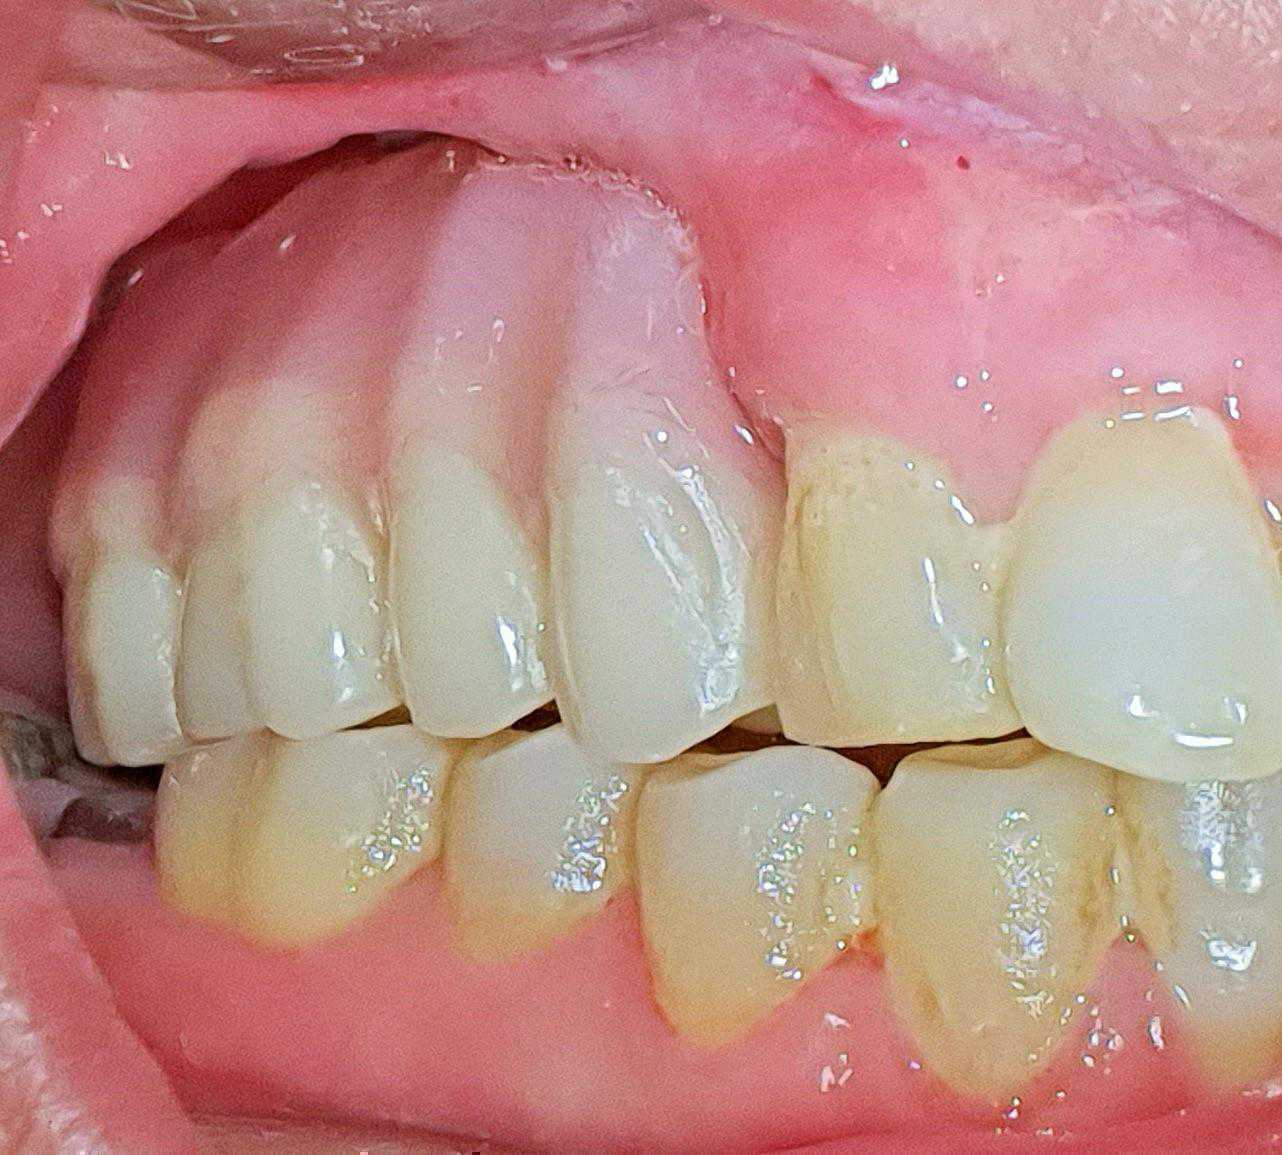

https://demo.discussdentistry.com/forums/topic/post-mucormycosis-avascular-necrosis-of-maxilla-rehabilitation-with-zygomatic/#post-24499 <![CDATA[Post Mucormycosis Avascular necrosis of maxilla, rehabilitation with Zygomatic]]> https://demo.discussdentistry.com/forums/topic/post-mucormycosis-avascular-necrosis-of-maxilla-rehabilitation-with-zygomatic/#post-24499 Thu, 25 Aug 2022 12:14:40 +0000 Sankalp Mittal

• 20210604_101325 (2)20210604_101317 (2)20210604_103315 (2)20210604_102857 (2)20210604_104202 (2)20210604_104853 (2)20210824_105656 (2)20210824_112353 (2)20210824_114957 (2)20210824_131302 (2)20210826_100648 (2)20210826_100749 (2)20210826_100919 (2)20210914_183943 (2)20211001_17535220211012_18543620211012_192043 (2)20211012_185627 (2)20211012_195430 (3)20211027_193725 (2)20211027_200729 (2)20211027_200919